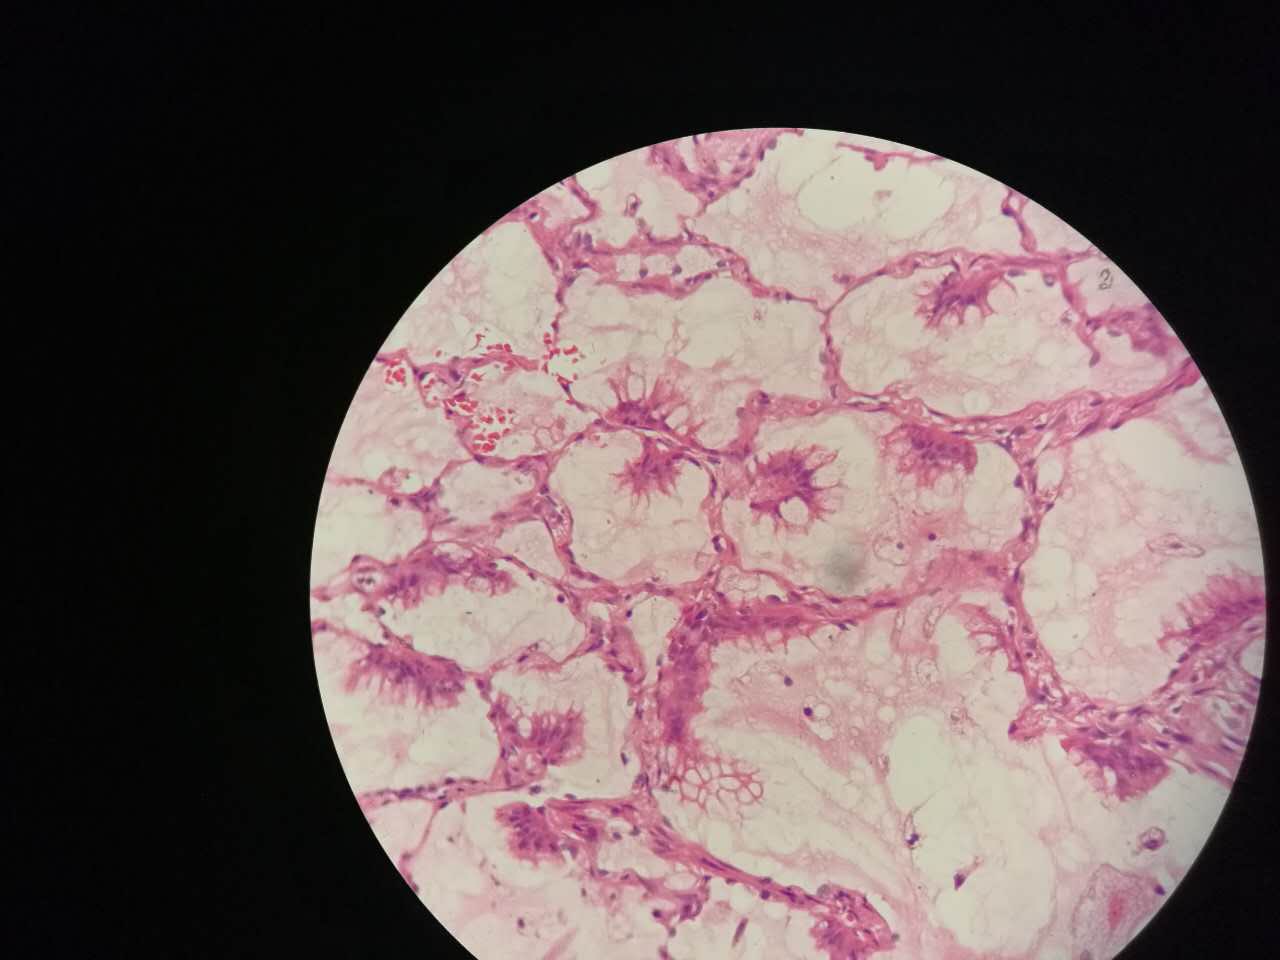

这个是早期结节状的粘液型腺癌

随着粘液近距离播散

早期粘液漂散也是近距离的,右侧肺泡里干净,没粘液,粘液产量有限,并且互相有黏连牵制。

所以结节性粘液腺癌边界一般较清楚

粘液型腺癌的肿瘤细胞排列整齐,核位于基底,细胞呈柱状。

肺泡间隔(间质)经常比较细

差不多都长这样

这个生长密集,相对要重